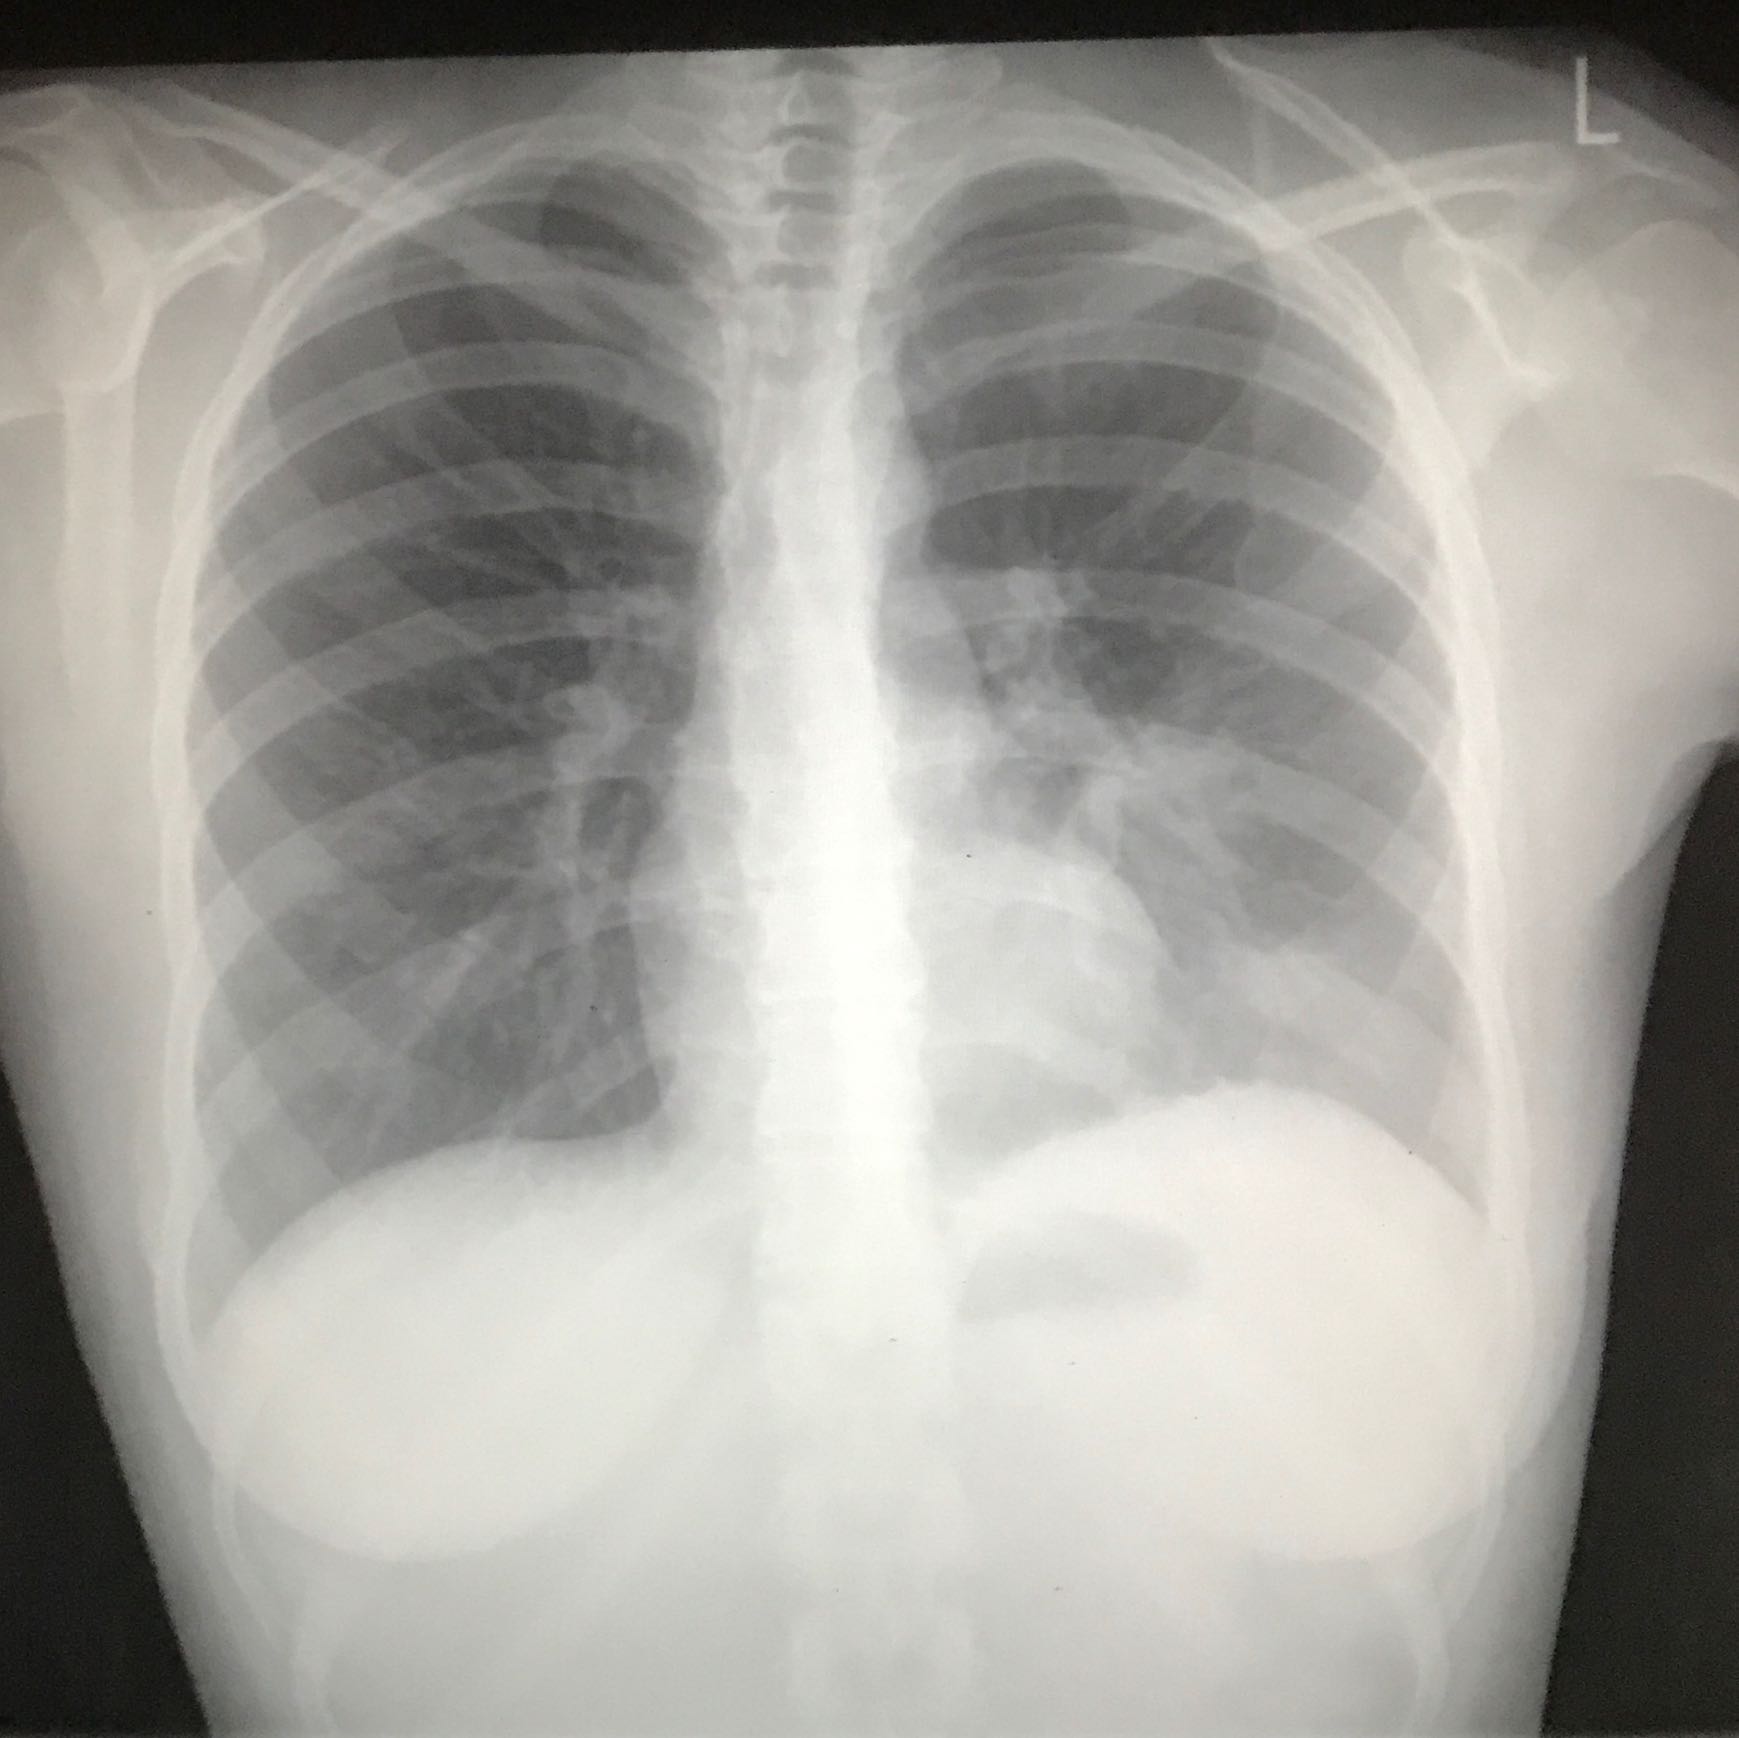

ThoraxRöntgen zur Diagnose von Lungenkrebs

Gesunde Lunge, Röntgen Stockfotografie Alamy